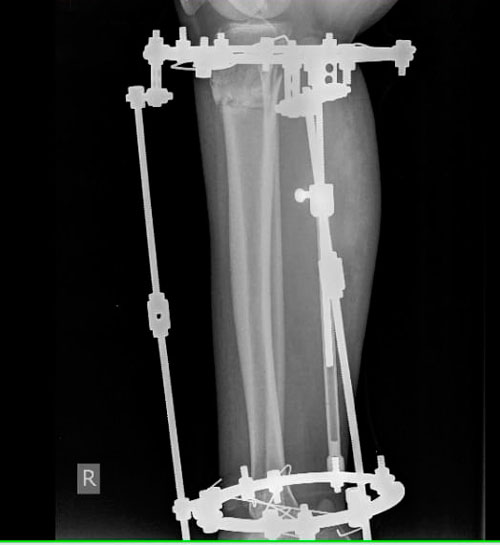

Рентген в 90дней.

Вложения

IMG_1444-25-02-19-05-32.JPG

IMG_1443-25-02-19-05-32.JPG

Дата операции -21.11.2018г.

Дата снятия аппаратов - 01.03.2019.

Срок сращения - 98 дней.